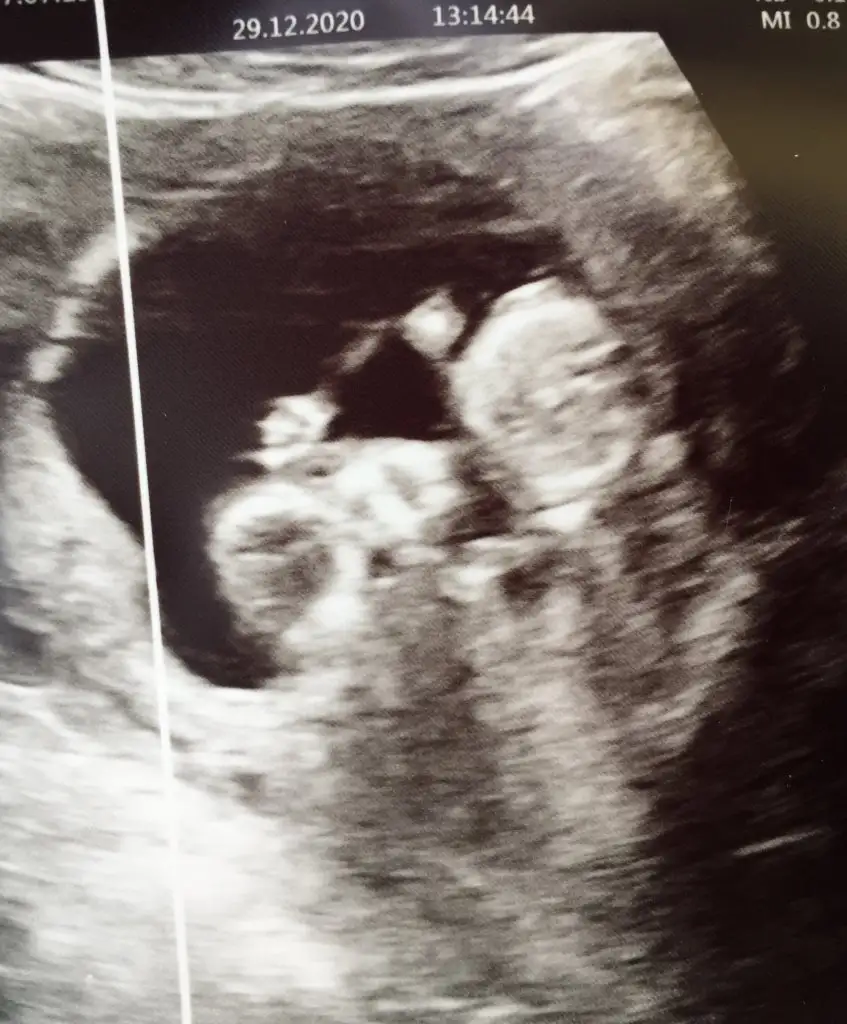

11+3 aslında ama 13te gidersem yine atarım canım 7. Haftaya kız demiştin hadi bakalım sağlıklı akıllı bebisler olsunlar da inşallahBebek baş aşağı yorum nasıl yapacam şaşırdım11 12 13 haftalar olursa paylaşın erkek gibi sanki bir uzantı var nubunda ama olmayabilir

Erkek görünüyorEki Görüntüle 2749723 Eki Görüntüle 2749724 Günaydın ikra meyra buna da bakarmısın 11+3

Canlar benimki küçük ama foto net bakabilir misinizIkra meyra 8 haftalık burda Eki Görüntüle 2749923

Başka USG varsa paylaşın nubu net degil

Yok maalesef doktorum bunları verdiBaşka USG varsa paylaşın nubu net degil

Bi tahmin alabilir miyim acabaBoyutsuz olursa daha iyi olur hiç net değil usgde

Başka USG varsa paylaşın net görünmüyorBi tahmin alabilir miyim acaba